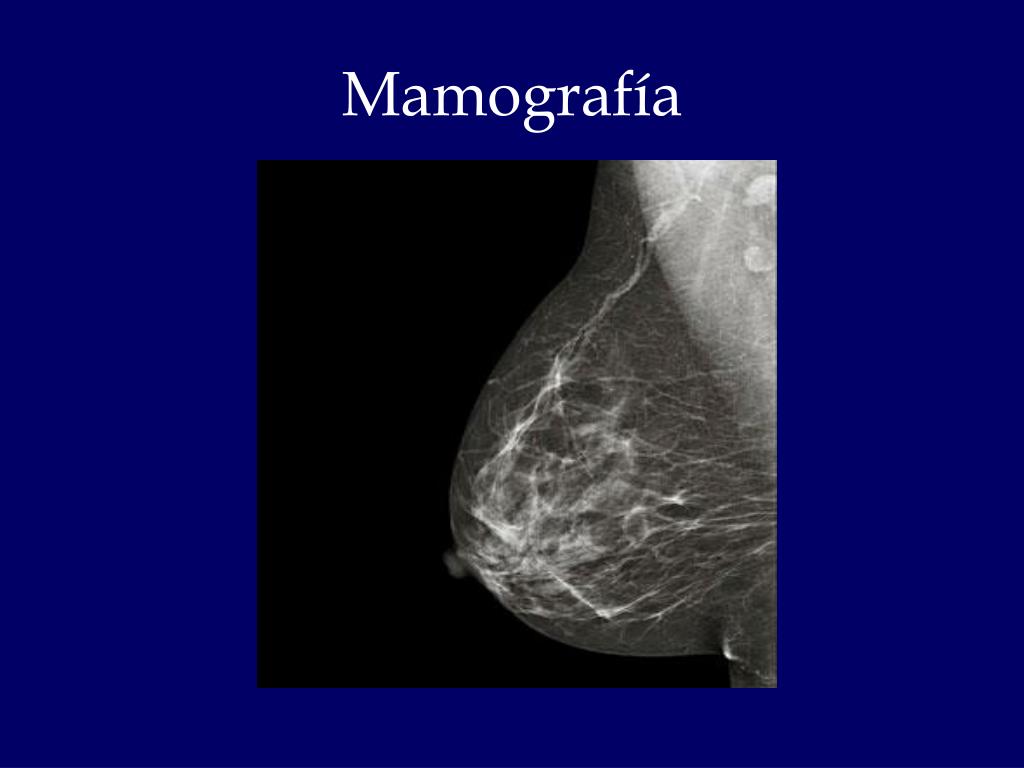

18. Anatomía clínica • Mamografía: es una exploración radiológica para la detección sistemática de quistes y tumores, tanto benignos como malignos. • Desempeña un papel muy importante en el diagnostico precoz del cáncer de mama • Cáncer de mama: se origina en el cuadrante lateral superior [60% de los casos], y da lugar a una masa palpable en los estadios avanzados, y afecta los ligamentos suspensorios de la mama o de Cooper, acortándolos, lo cual a su vez produce, depresiones o fosas en la piel que recubre la mama. Puede afectar también los conductos galatactoforos o lactíferos, con el correspondiente acortamiento de estos, lo que provoca la retracción o inversión del pezón. • Puede invadir la fascia profunda del pectoral mayor, de tal forma que la contracción del musculo provoca un movimiento repentino de la mama hacia arriba.

19. Mamografía